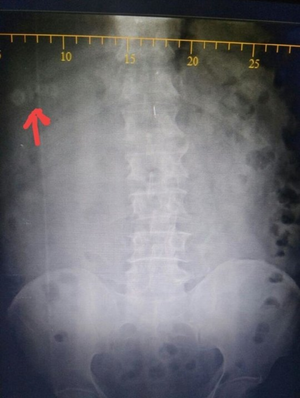

This is not a case,just a rare finding of visible gallstones on abdominal X-Ray.

10% of Gallstones are radio-opaque !! Confirmation by USG is necesarry for gallstones